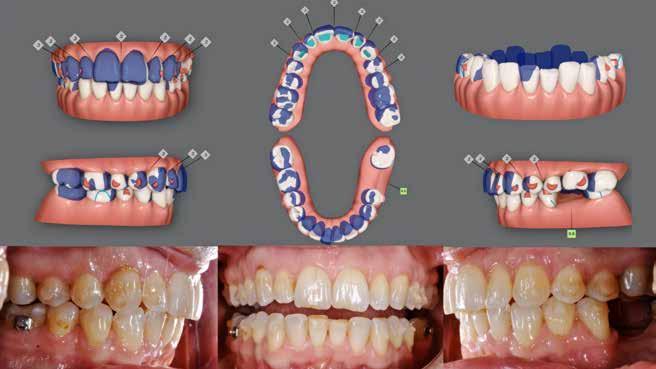

A. Ortodontisk behandling med intrusion og proklination af underkæbefronten er simuleret med visualisering af slutresultatet. B-D. Nivellering af Spee kurve, type og position af attachments, biteramps på overkæbeincisiver til mild bidhævning, distorotation og distalisering af siderne i overkæben.

2. A. Orthodontic treatment with intrusion and proclination of the lower front simulated with visualisation. B-D. Leveling of the Spee curve, type and position of attachments, bite ramps on maxillary incisors for mild bite elevation, distorotation and distalization of the sides in the maxilla).

Der planlægges alignerbehandling af begge kæber med intrusion af 1+1 og 2,1-1,2, nivellering af trangstilling UK med interproksimal reduktion (IPR) (Fig. 2 A, B) og senere IPR OK for reduktion af dark triangles mellem incisiverne efter nivellering. Patienten instrueres i at benytte alignere 20-22 timer/ dag med alignerskift hver 7. dag, og patienten ses hver 3.-8. uge under forløbet. Den første alignerserie består af 16 alignere for nivellering OK/UK og IPR i UK (Fig. 2). Efter denne serie planlægges IPR mellem incisiverne i OK for reduktion af dark triangles (Fig. 3) samt yderligere intrusion af OK og UK-fronten i 12 refinement-alignere. Patienten udviser god kooperation og er meget tilfreds med alignerapparaturet, som er mindre synligt end det faste apparatur (Fig. 4).